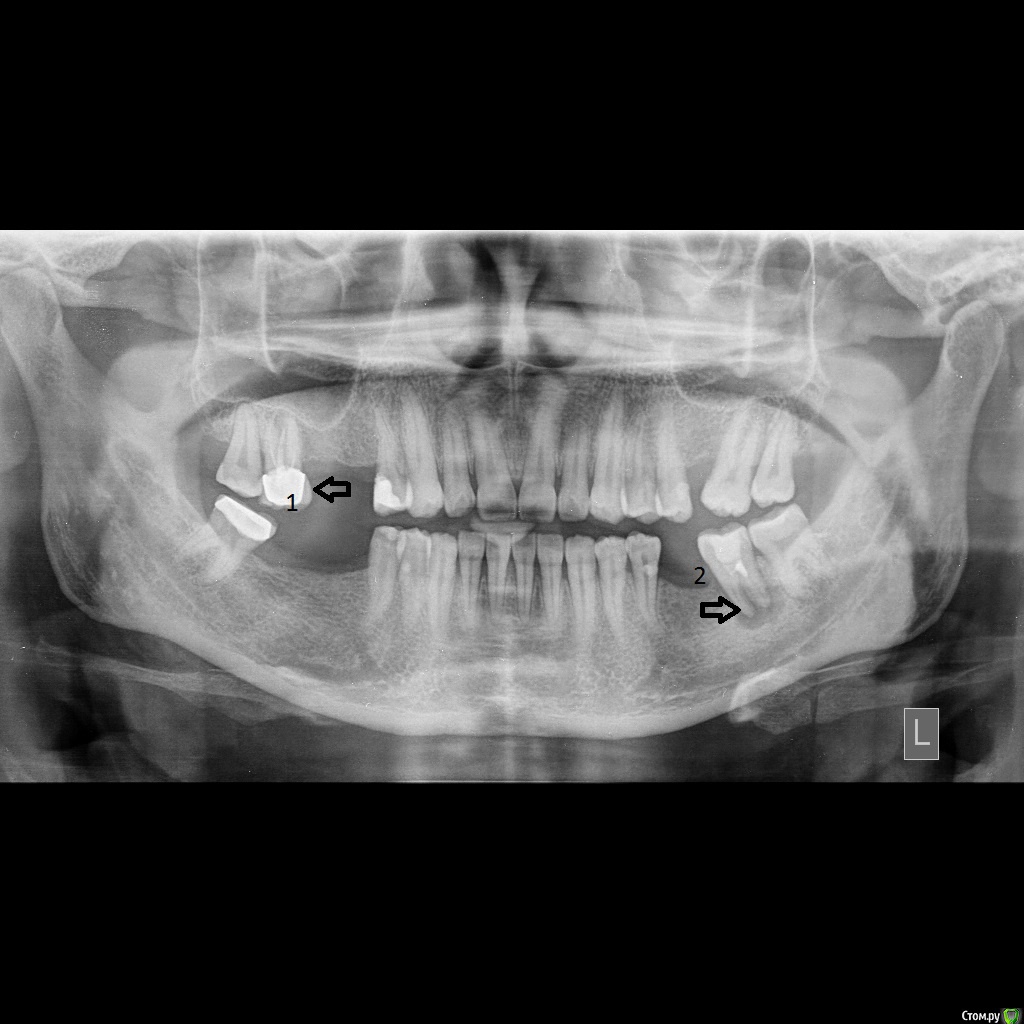

Справа сверху появился неприятный привкус и запах, сделал панорамный снимок. Врач сказал что проблема в двух местах, но так как привкус возникал справа, то удалил верхний предпоследний правый зуб (номер1)

Через месяц после удаления начал снова замечать привкус в том же месте. Врач говорит что проблема точно из за зуба 2.

Добрый день. Неприятный запах может быть связан с разными причинами. Например  бывает при наличии "камней" и других проблем с десной (тогда нужно делать чистку у парадонтолога), когда есть разрушенные зубы и старые коронки(тогда их по ситуации или переделывают или удаляют), а может быть запах от состояния ЖКТ (и тогда это уже не к стоматологам).

Зуб отмеченный цифровой 2 не может давать описаные жалобы. Проблема в нем в воспалении за пределами корня. В нем нужно перелечивать каналы. Ну и еще что то думать на место отсутствующих зубов чтоб не скалывались передние от перегрузки